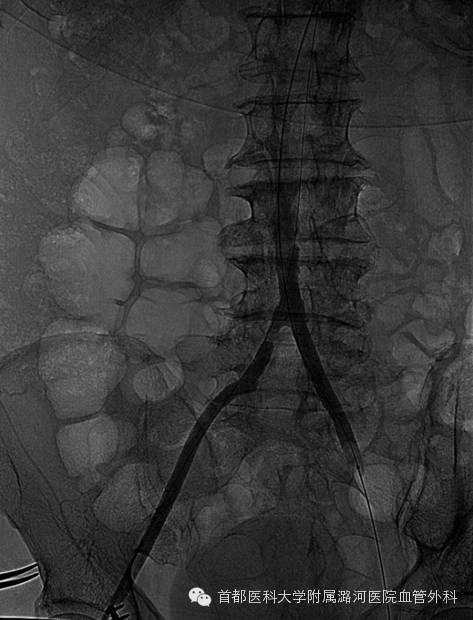

为了验证术前诊断的准确性,左侧肱动脉穿刺,腹主动脉下缘置入猪尾导管造影显示:

右侧髂总动脉起始段至髂外动脉末端全程闭塞